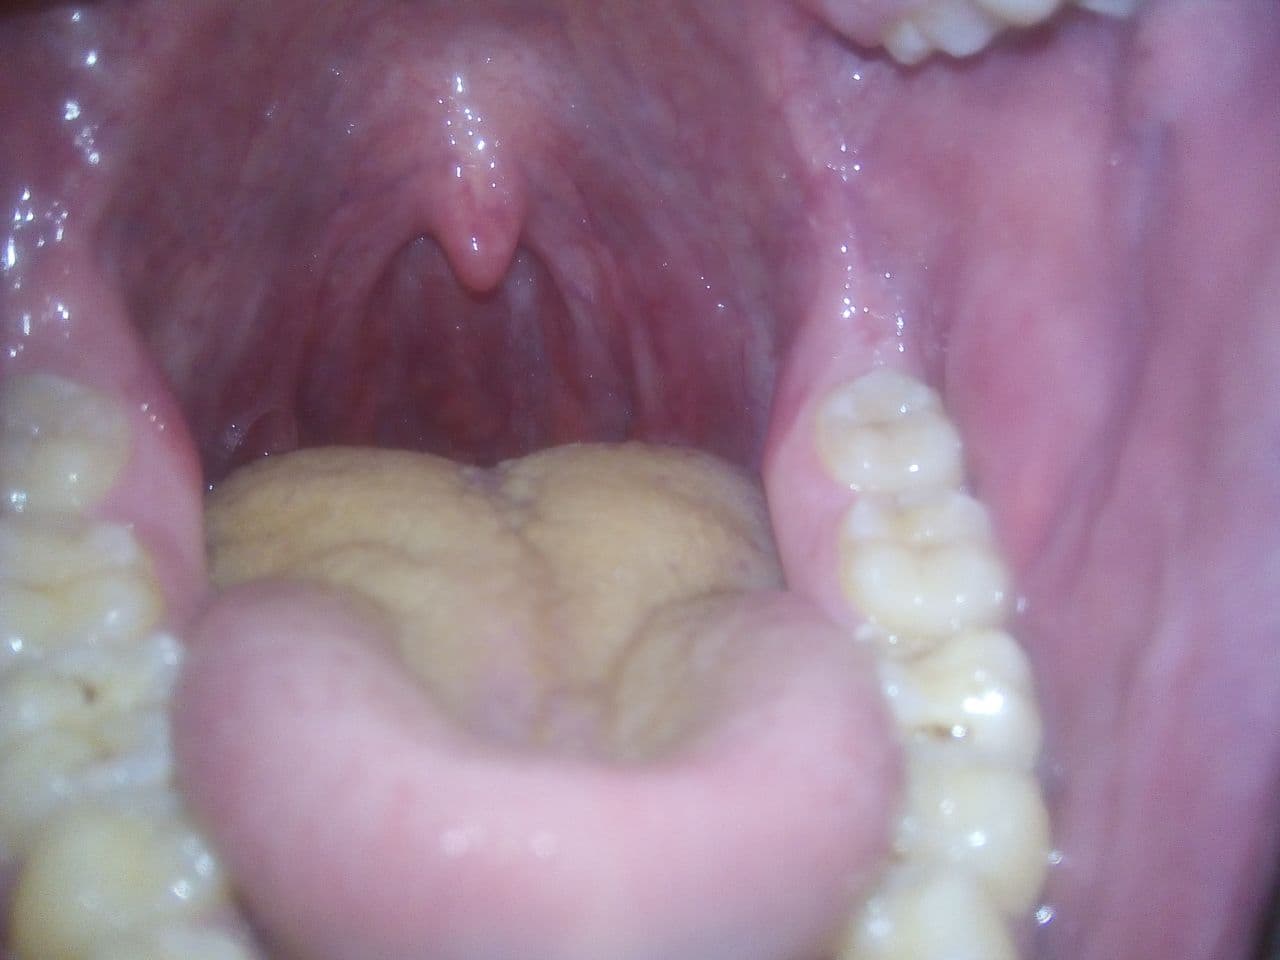

C4CA05D2-5582-4DE5-912C-D2DABB74D4EE.jpeg

42960C18-BD43-4233-9EAD-A0F82B71DAF9.jpeg

Сап, двач. Три дня назад выскочила такая хуета во рту. Похоже, будто откусил себе часть щеки, и теперь она вниз свалилась. До этого с таким не сталкивался. С утра, когда сильный сушняк (принимаю на ночь Кветиапин), болит, потом не очень, но глотать больно. Что это может быть? На обычный стоматит не похоже.

>>1251820

Действительно, прикусил. Избегать холодной, горячей пищи и напитков. Полощи антисептиком, тип хлоррофиллипт. Через несколько дней пройдет. Будет часто повторяться, нужно будет обратиться к стоматологу.

анон-лор-кун